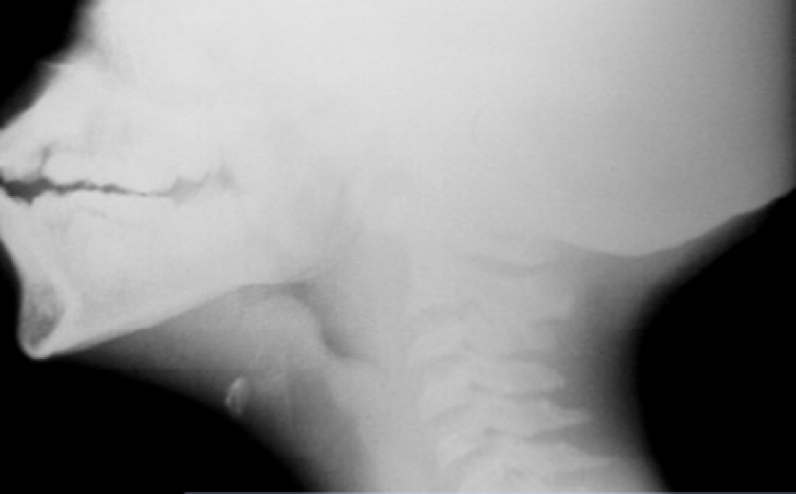

Sample Test item 1/multiple questions.  What is the diagnosis?  What are the radiographic signs you see? what would you expect to find on physical examination? What is contraindicated?  Is anything indicated on an emergency basis?  What is the MC cause?  Is there any ancillary treatment after the emergency has been managed?

Test Item 1 Answers:  No this is not croup, it is epiglottitis. Signs of epiglottitis seen on this upright lateral film:  Child is sitting upright in the sniffing position.  The neck is straight and angled forward at the base of the neck to make the head shift forward.  You see a dilated hypopharynx and can’t visualize the valecula as it is filled with swollen epiglottis.  The epiglottis is oriented horizontally from edema, i.e., you see the thumbprint sign.  This patient needs controlled intubation, ideally performed immediately in the operating room.  On physical exam you may see a febrile, drooling child who is noncommunicative with a muffled voice and only focused on breathing, i.e., he/she is quiet.  The child may be maintaining an upright posture in a tripod position and refuse to lay down while holding both arms extended at the sides.  You may hear gross inspiratory stridor.  Nothing should be done prior to the intubation as it may worsen the child’s condition and cause complete obstruction of the airway.  If loss of the airway occurs most can initially be ventilated with an Ambu bag and mask.  The next choice is needle cricothytomy and/or emergency intubation.  If the child tolerates it, a face mask with oxygen can be held just in front and below the face prior to the intubation in the O.R.  The MCC is S pneumoniae.  Hemophlius type B was the primary cause in children prior to the introduction of the Hemophilus vaccine.  However, there are periodic outbreaks of Hemophilus infections due to failure to vaccinate children. Also the most common age for this condition in children has changed from three years to eight – twelve years. Ancillary treatment:  An IV line is not started until after an ET tube has been secured to avoid complete airway obstruction.  Next a 3rd generation cephalosporin (either cefuroxime, ceftriaxone, or cefotaxime) should be administered and the child admitted to an ICU.  A pneumococcal vaccine and/or Hib vaccine may is indicated. …from Visual Test Items [VSTIs] to be released as a new chapter section in my book The Complete EM Board Prep! © D Collman 2023. I hope to publish this text in 2023-over 600 pages! Look for it in the Fall of 2023.! Reserve your copy now!. This is everything I have ever taught or written about for 40 years to prepare you for the ABEM certifying exam, the ConCertTM exam, and the oral exam in emergency medicine. Completely updated in 2023.!